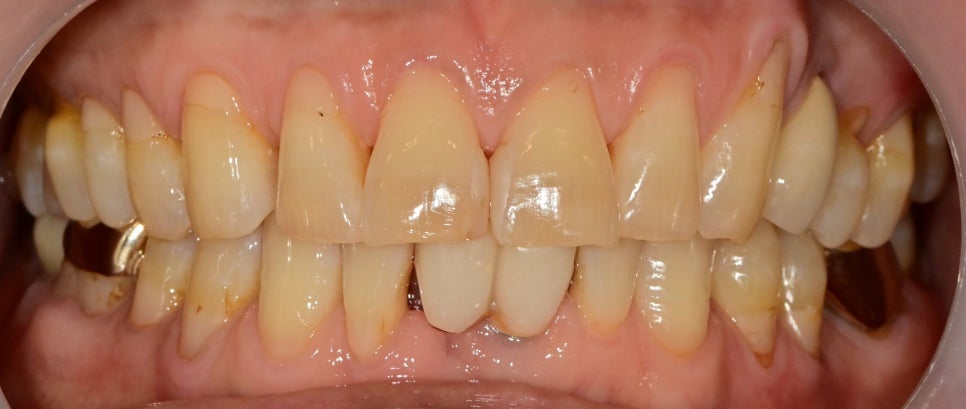

수술 후 직후의 모습입니다.

앞니 임플란트의 수술 즉시 임시치아는

씹는 용도가 아니고 빈 공간을 채워주는 것이 목적이기

때문에 위 치아와 교합을 조정해 주고 잇몸 경계에 맞춰

임시치아를 수정했습니다.

물론 최종 보철물처럼 색상을 다 맞출 순 없지만

뺐다 꼈다 하는 임시틀니를 끼는 것보다는 훨씬

자연스럽다고 말씀해 주십니다.

수술 후 최종 보철까지 완성 소요 시간

수술 후 최종 보철물까지 3달 정도가 소요되었습니다.

치조골이식부위도 볼륨이 잘 유지 되어있고

보철물 라인도 자연스럽게 제작되었습니다

임시치아 때보다 색상은 주변 치아와 맞춰졌고

수술후 붓기가 가라앉은 잇몸에

맞춰 치아 형태도 제작이 되었습니다.